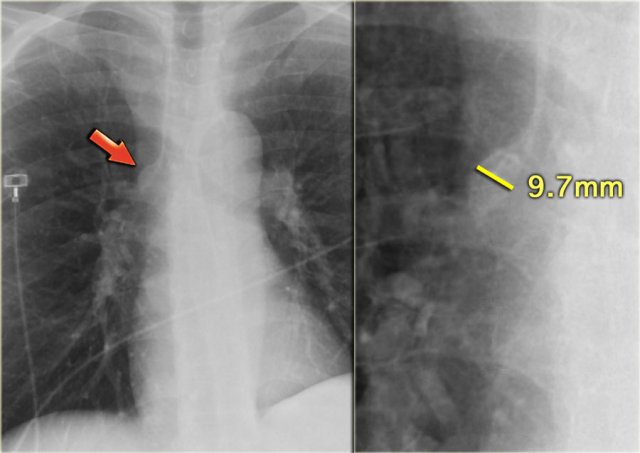

On the left a patient with cardiomegaly and redistribution.

The upper lobe vessels have a diameter > 3 mm (normal 1-2 mm).

Notice the increased artery-to-bronchus ratio at hilar level (arrows).